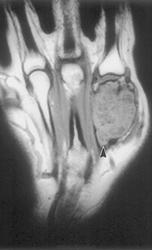

Злокачественная гигантоклеточная  опухоль возникает из доброкачественной (частота 10-20%). После операции возможно появление рецидива опухоли.

Гигантоклеточная опухоль